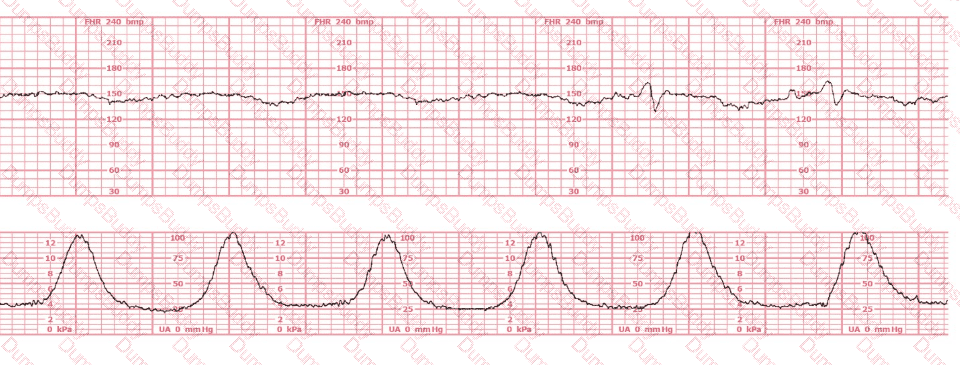

A woman has been 5 cm dilated for the past 3 hours. The tracing shown has developed over the last 30 minutes. The best initial course of action is to:

This patient received an epidural 15 minutes prior to the tracing shown. The next course of action is to: